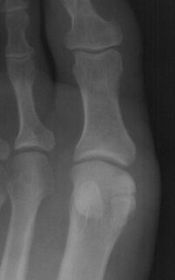

Describe the alignment of metatarsal 2 | There is no angulation nor displacement of the distal segment relative to the proximal segment. |

Describe the alignment of metatarsal 3 | The distal segment is displaced laterally (50% apposition) and angulated medially. |

Describe the alignment of metatarsal 4 | The distal segment is displaced laterally (75% apposition) but there is no apparent angulation. |

Describe the tubulation of the metatarsals | Metatarsals are overtubulated - decreased girth. |